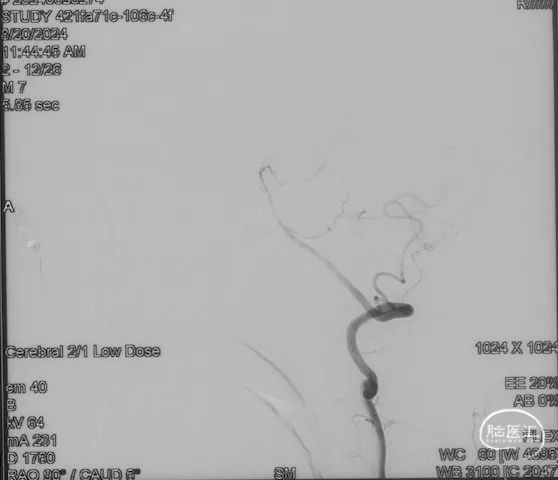

术前造影

证实为TDAVF,为岩上窦型。R-ECA正侧位见右侧脑膜中动脉分支、枕动脉分支、颞浅动脉分支向瘘口供血,经幕上迂曲扩张的静脉、中脑周围静脉、基底静脉向深部静脉引流。

R-ICA正侧位见右侧脑膜垂体干向瘘口供血

L-ICA正侧位见左侧脑膜垂体干分支向瘘口供血

L-ECA正侧位未见向瘘口供血

L-VA、R-VA正侧位右侧小脑上动脉脑膜支向瘘口供血

选取工作角度,正侧位造影